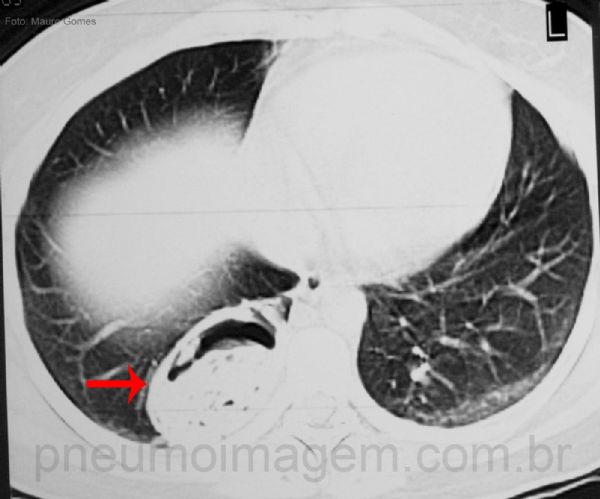

Apresenta-se como massa pulmonar ou opacidades policísticas, geralmente localizadas nos segmentos basais posteriores dos lobos inferiores.

Mass or polycystic opacities, usually located

in the posterior basal segments of the lower lobes.

Os sequestros podem ser assintomáticos e diagnosticados por suspeita de neoplasia pulmonar em achado radiológico ou ocasionam tosse produtiva crônica, infecções pulmonares de repetição, hemoptise e dor torácica. Neste corte tomográfico observa-se a lesão posteriormente e a formação em crescente permite confundir com aspergiloma.